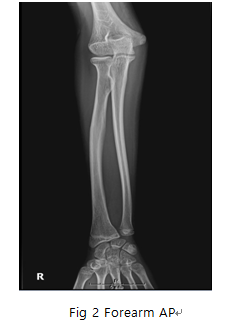

Forearm AP

- ulna과 radius의 fracture 및 fracture에 따르는 elbow joint과 Articulations of hand의 변위 등의 병변 유무를 관찰한다.

6) 영상 결과

① Articulations of hand와 elbow joint 포함

② radial head, neck of radius, radial tuberosity의 ulna Proximal part에 일부 겹침

③ humerus epicondyle의 확대유무 확인

④ forearm의 균일한 영상농도

- dislocation 주의 , Articulations of hand과 elbow joint의 포함.